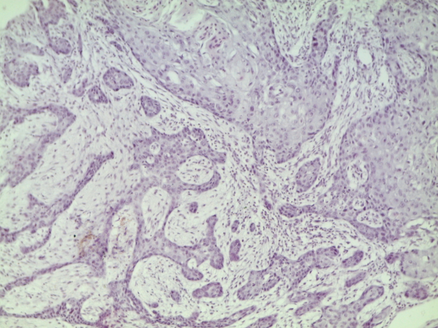

Препарат № 139.

ПЛОСКОКЛЕТОЧНЫЙ ОРОГОВЕВАЮЩИЙ РАК (ПИЩЕВОДА)

Окраска: гематоксилин-эозин

Пласты и тяжи атипичного плоского эпителия врастают в подлежащую соединительную ткань и в мышечную оболочку пищевода. В центре пластов происходит ороговение эпителия – образуются так называемые «раковые жемчужины». В строме опухоли инфильтрация преимущественно лейкоцитами и плазматическими клетками. Обратить внимание, что в имеющихся в препарате небольших лимфоузлах метастазов еще нет.

Отметить:

1. Атипичные эпителиальные пласты

2. Лимфоузел

3. «Раковые жемчужины».